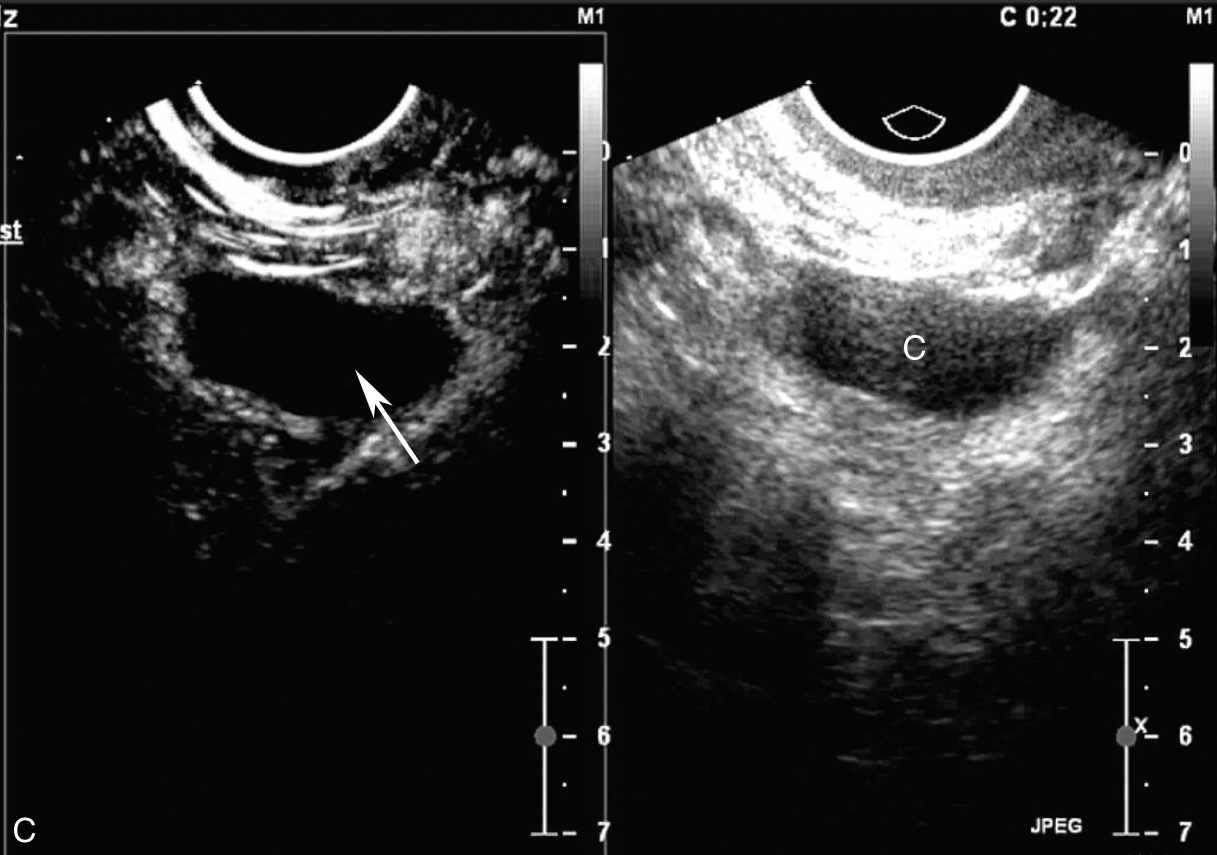

经阴道超声检查见图3-12-2。子宫前位,宫体大小为4.6cm×6.5cm×5.6cm,内膜居中,厚0.2cm(单层),肌壁回声欠均匀,未探及明显异常血流。宫颈查见囊性占位,最大径约3.1cm,液体欠清亮,周边未探及血流信号。右卵巢上查见囊性占位,大小为3.0cm×1.6cm×2.5cm,囊液欠清亮,囊壁可探及血流信号。左附件区未见占位。超声检查结果:右卵巢上囊性占位(多系良性),子宫颈腺囊肿。

图3-12-2 常规超声声像图

A.前位子宫的矢状切面;B.子宫横切面;C.右附件区囊性占位;D.宫颈囊性占位。UT:子宫;C:囊肿;Cx:宫颈。